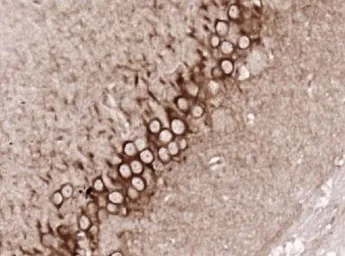

ApplicationsWB IHC-P IHC-Fr FCM

ReactivityHuman, Mouse, Rat